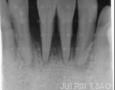

Pictures

Baseline